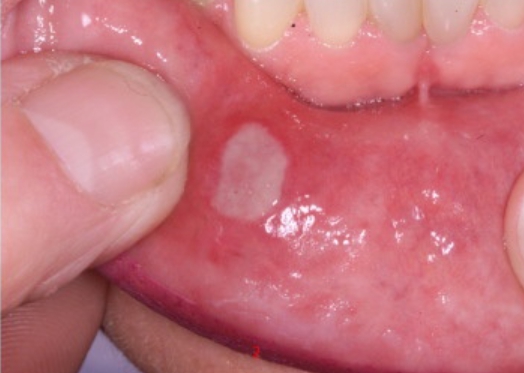

구내염은 단순한 입안 염증으로 생각하기 쉽지만, 사실 신체가 보내는 중요한 경고 신호일 수 있습니다. 단순히 매운 음식을 먹거나 뜨거운 음식에 데어서 생기는 일시적인 상처가 아니라, 만성적으로 구내염이 반복된다면 우리 몸이 내부적으로 불균형을 겪고 있다는 뜻입니다.

구내염의 가장 큰 원인은 면역력 저하입니다. 면역력이 약해지면 우리 몸은 바이러스나 박테리아와 싸우는 능력이 떨어지는데, 이때 가장 먼저 영향을 받는 곳이 입안의 점막입니다. 구강 점막은 피부보다 얇고 예민하기 때문에 면역 체계가 무너지면 쉽게 염증이 생기고 상처가 납니다. 특히, 잠을 충분히 자지 못하거나 과도한 업무와 스트레스로 인해 몸이 지치면 구내염이 자주 발생합니다.

우리 입속에는 수많은 세균이 존재하며, 유익균과 유해균의 균형이 유지될 때 건강한 구강 상태를 유지할 수 있습니다. 그러나 면역력이 저하되거나 구강 청결이 제대로 관리되지 않을 경우 유해균이 증가하면서 염증이 발생할 가능성이 높아집니다. 구내염이 자주 생기는 사람들은 양치 습관을 점검하고, 항균 성분이 포함된 가글액을 적절히 사용하는 것이 도움이 될 수 있습니다.